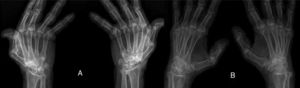

ResultsWe could include 230 patients (female 177 (77%) and males 53 (23%)) with established RA, fulfilling the 2010 ACR/EULAR classification criteria for RA.12 Their mean age was 47.06±11.75 years and disease duration 64.11±54.72 months. RF was positive in 101 (43.9%) and ACPA was positive in 220 (95.7%), while ANA was positive in 58 (25.2%), anti-Ro/SSA in 31 (13.5%), anti-La/SSB in 10 (4.3%), anti-RNP in 2 (.9%) and none of the patients showed anti-Sm antibodies. Anti-Jo-1 was positive in 5 (2.2%), none of them had increased CPK levels and all five cases showed typical erosive changes consistent with the diagnosis of RA (Fig. 1). Two out of the 5 cases with positive Anti-Jo-1 had ILD (Figs. 2 and 3). Detailed demographic features, clinical manifestations, laboratory investigations, SHS, drug therapy and disease activity scores are summarized in Table 1. In the controls (n=75), RF (low titer) was positive in 4, ANA was positive in two (2.7%), anti-Ro/SSA in three (4%), and none of the control group tested positive for anti-La/SSB, anti-Sm, anti-Jo-1, anti- U1RNP autoantibodies and none tested positive for ACPA.

(A) First RA case with anti-Jo-1 positive and showing the typical radiological features of RA in the form of intercarpaljoints, radio-carpal, and carpometacarpal joints erosions PIPs and MCPs erosions with juxta-articular osteoporosis and decreased joint spaces, MCPs subluxations and Z thumb deformity; (B) Second case with RA, and positive anti-Jo-1 showing intercarpal, radio-carpal, and carpometacarpal joints erosions, PIPs and MCP jointserosions with juxta-articular osteoporosis and joint spaces narrowing, consistent with the diagnosis of RA.